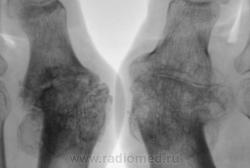

Пациентка направлена на рентгенографию стоп в прямой проекции с диагнохом - "Поперечное плоскостопие".

Произведена рентгенография обеих стоп в прямой проекции.

Думаю, что это дисхондроплазия - болезнь Олье.

Сильно сомневаюсь в болезни Олье - затронуты только суставные концы, диафизы интактны. Считаю - остеоартропатия, вероятнее всего - подагра

Классика подагры - наличие тофусов в параартикулярных мягких тканях... Механизм поражения скелета при подагре - атрофия от давления тофусами. А здесь - их совершенно не видно, мягкие ткани просто отодвинуты, но обьем то их - нормальный...

Согласен с артропатией, но подагра - сомнительно....

Поскольку артропатий великое множество....почему бы и не псориатическая...к примеру. Как там с анамнезом?

Пациентка весьма преклонного возраста - за 70 лет.